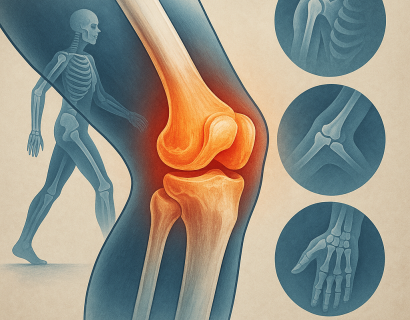

Мениски — это полулунные хрящевые прокладки, и, несмотря на их эластичность и прочность, они довольно часто повреждаются.

Коленный сустав — один из самых сложных и уязвимых суставов в человеческом теле. Он несёт огромную нагрузку каждый день, особенно у активных людей и спортсменов.